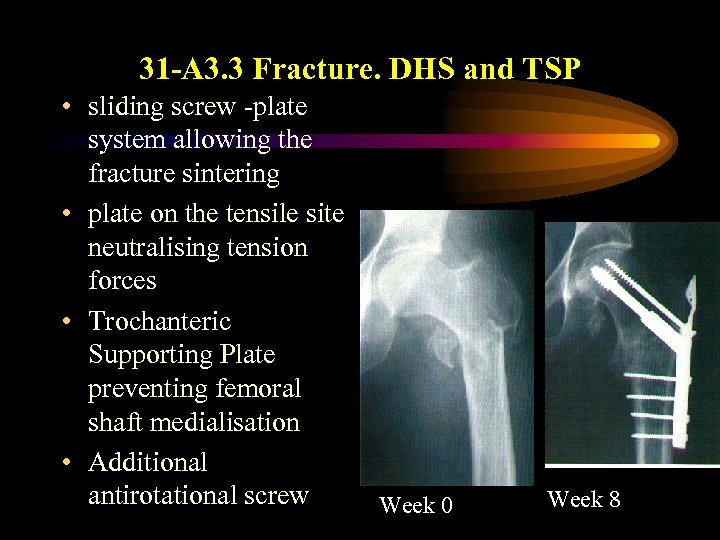

31 -A 3. 3 Fracture. DHS and TSP • sliding screw -plate system allowing the fracture sintering • plate on the tensile site neutralising tension forces • Trochanteric Supporting Plate preventing femoral shaft medialisation • Additional antirotational screw Week 0 Week 8

31 -A 3. 3 Fracture. DHS and TSP • sliding screw -plate system allowing the fracture sintering • plate on the tensile site neutralising tension forces • Trochanteric Supporting Plate preventing femoral shaft medialisation • Additional antirotational screw Week 0 Week 8